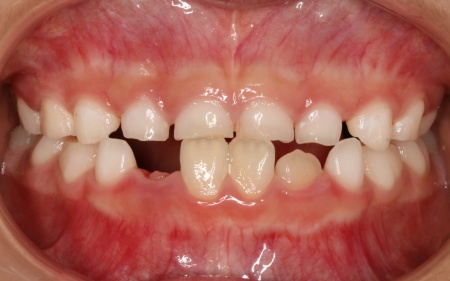

治療前

診断結果 拝見したところ、患者様は乳歯のみが生えている乳歯列期の段階でしたが、この時点ですでに反対咬合が認められました。

反対咬合とは、下の前歯が上の前歯よりも前に出ている状態のことで、一般的に「受け口」とも呼ばれます。